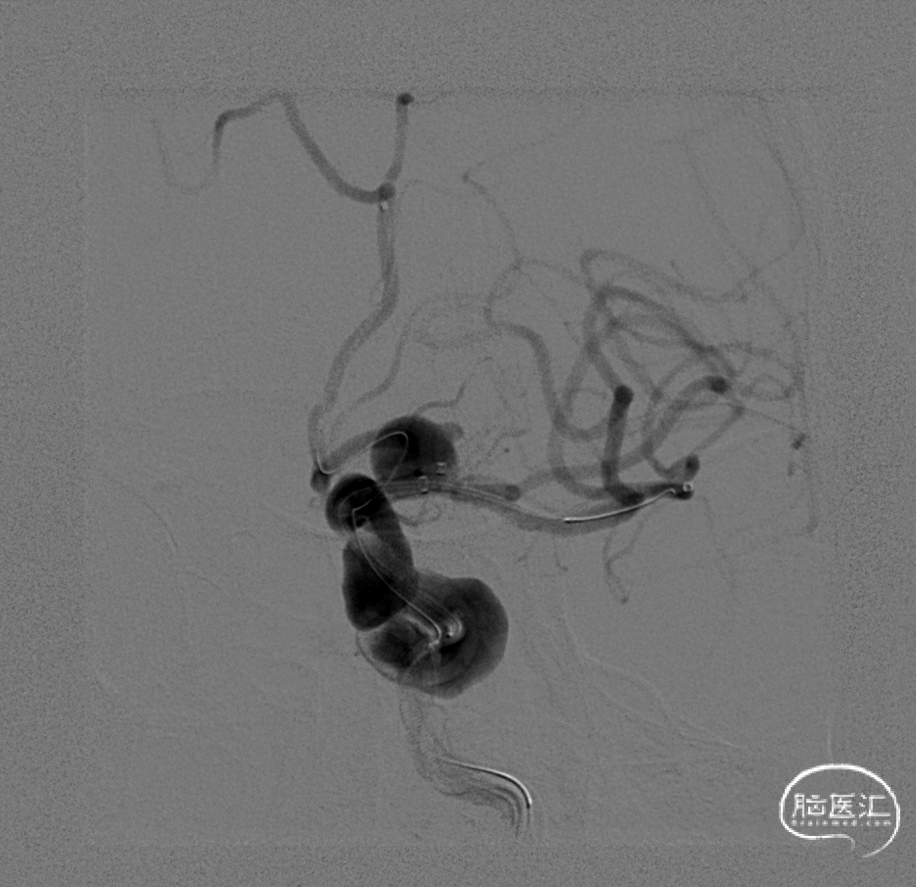

再次在微导丝引导下将Phenom 27 微导管送入第二枚Nuva®TJED-D-5.0-16血流导向密网支架,于海绵窦段开始原位释放密网支架,支架远端与Nuva®TJED-D-6.5-40血流导向密网支架部分重叠,继续缓慢释放支架,近端着陆于岩骨段。

造影观察血流及支架展开及贴壁情况。

发现岩骨段远端展开欠佳,导丝按摩后交换长导丝,采用颅内球囊扩张导管(2.0mm×15mm)处理展开欠佳处,扩张支架后见支架未完全展开处明显改善,造影见支架内血流通畅,动脉瘤腔内造影剂滞留。